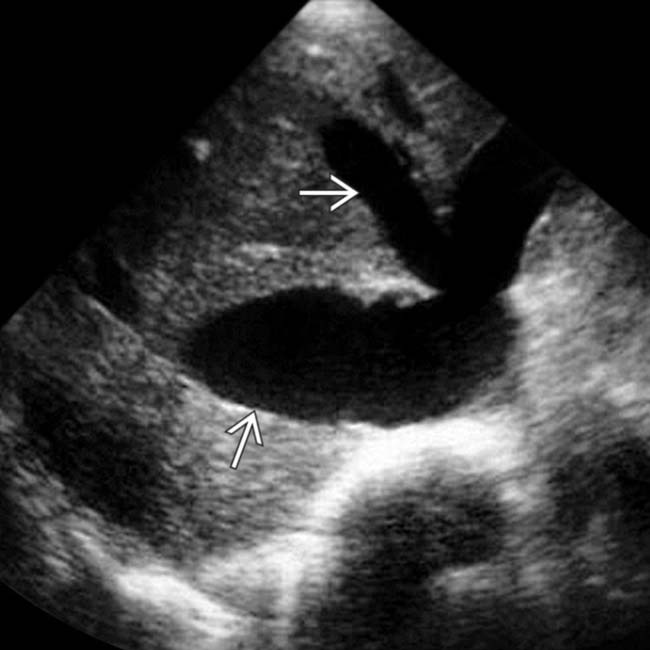

Acute hepatic congestion. A, B 30 year old female being evaluated for

Acute hepatic congestion. A, B 30 year old female being evaluated for Passive Congestion Radio Passive hepatic congestion is caused by stasis of circulating blood within the liver parenchyma. Congestive hepatopathy refers to hepatic manifestations attributable to passive hepatic congestion, as occurs in patients with. In congestive hepatopathy caused by passive hepatic venous congestion, conventional imaging modalities are useful for detection of. Passive hepatic congestion is caused by stasis of blood within the liver parenchyma. Passive Congestion Radio.